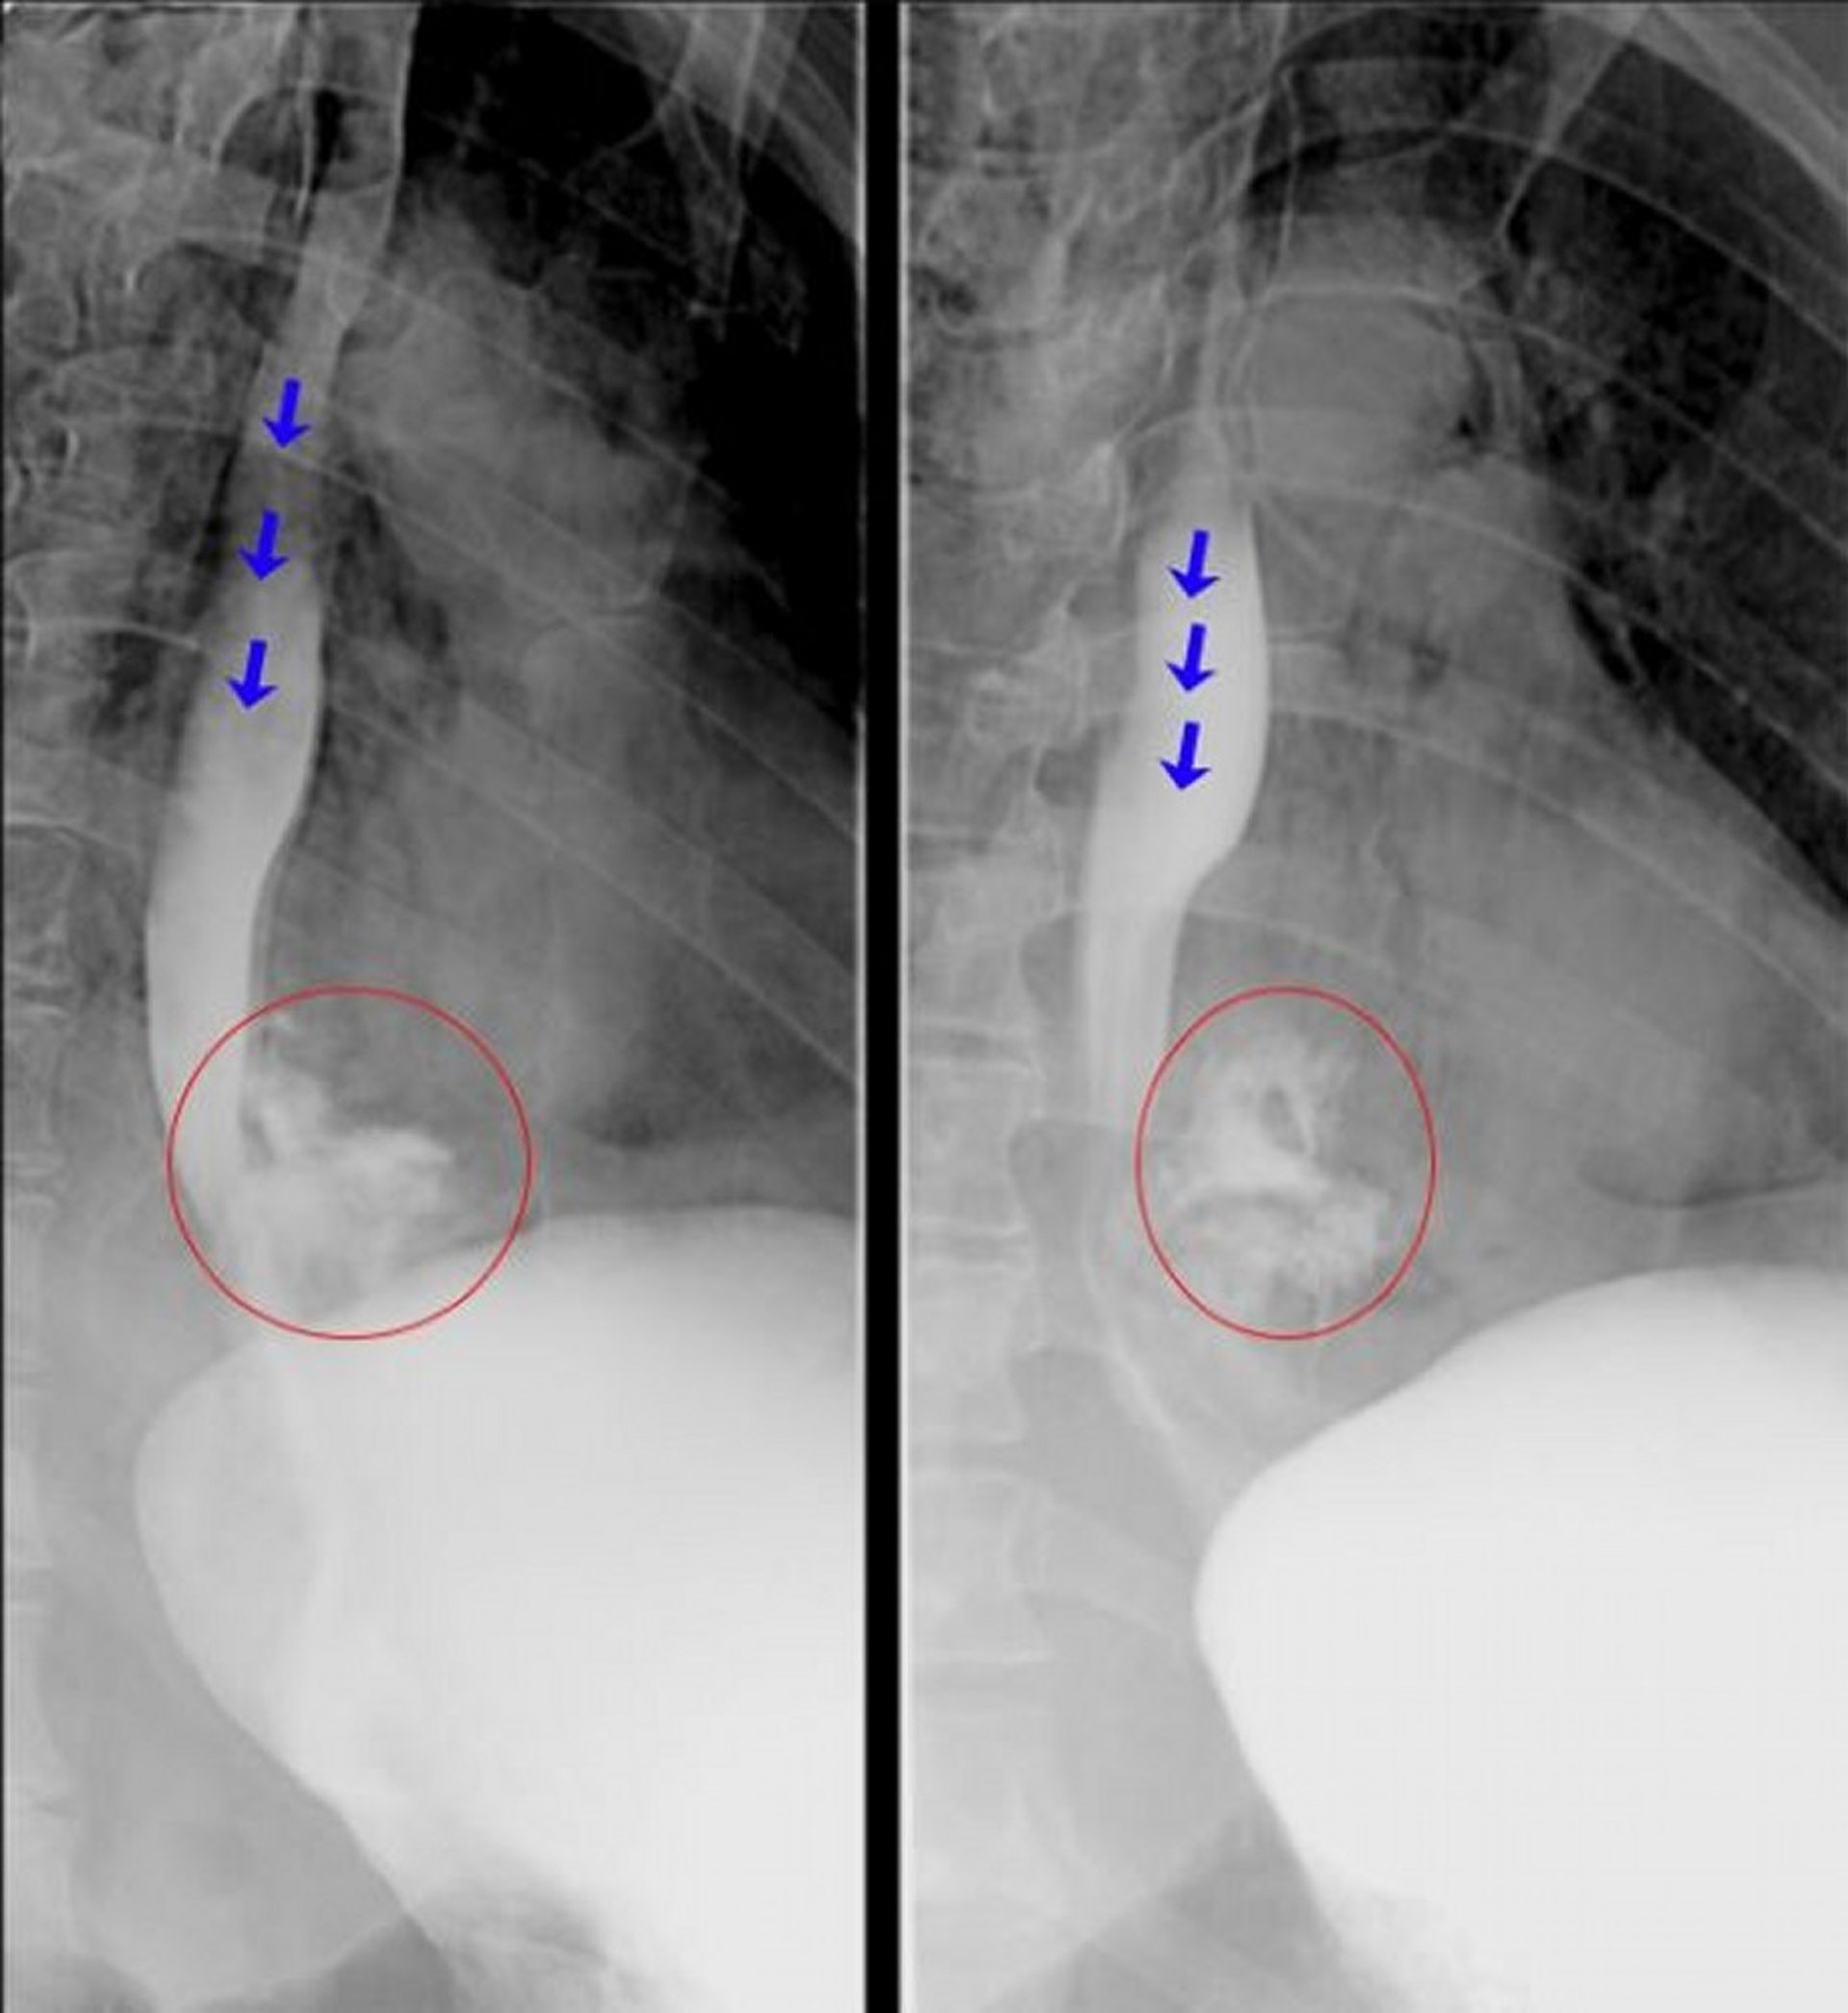

Esophagography with Water-Soluble Contrast

These fluoroscopic esophagograms show frank extravasation of contrast material from the distal esophagus consistent with an esophageal perforation. The blue arrows highlight contrast material within the lumen of esophagus. The red circles highlight contrast material that has extravasated out of the esophagus.